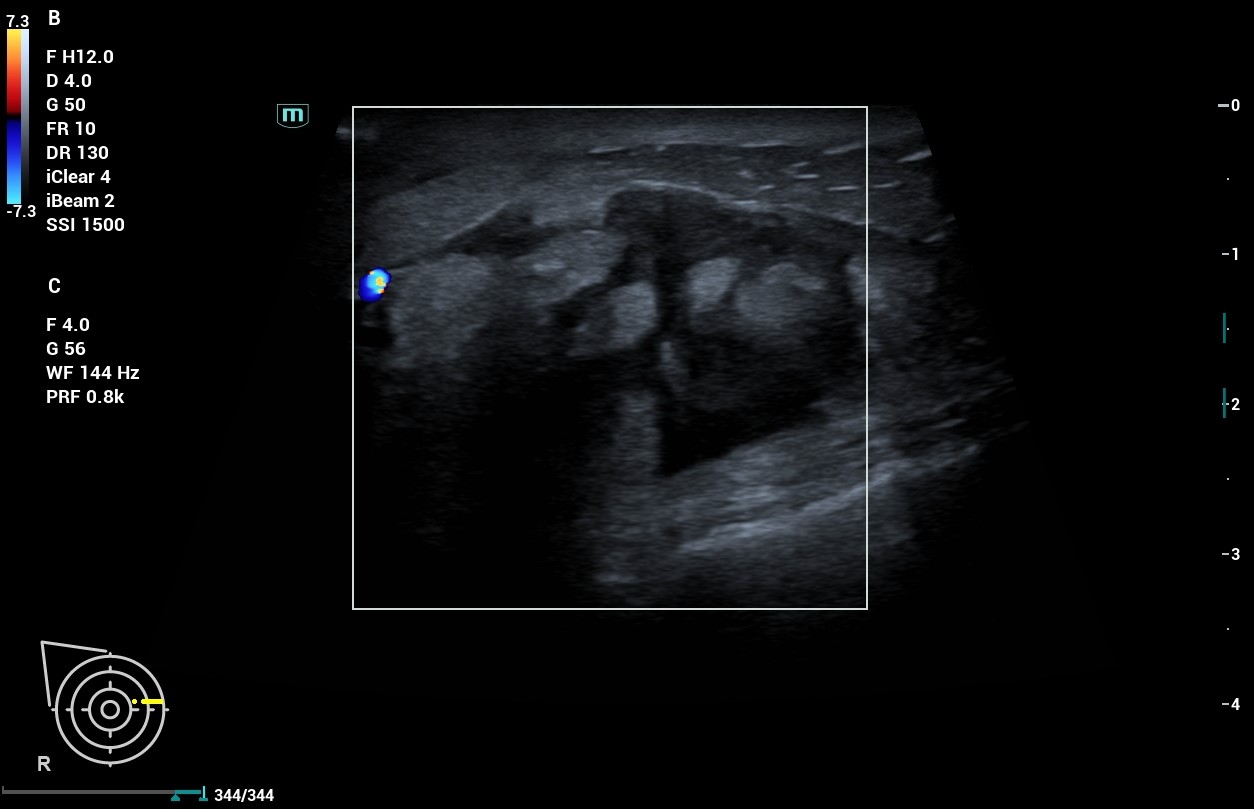

Al realizar ecografía observamos una imagen de 30 mm en cuadrantes internos de mama derecha que presenta bordes espiculados y contenido heteroecoico en su interior con áreas hipoecoicas.

Al tratarse de una lesión que presenta características de probable malignidad no solo en la exploración y anamnesis de la paciente sino a la confirmación con la ecografía, decidimos derivar a la paciente a Ginecología mediante circuito rápido, donde se confirma el diagnóstico de carcinoma ductal infiltrante de mama derecha G2, luminal B cT4bN3bM0.